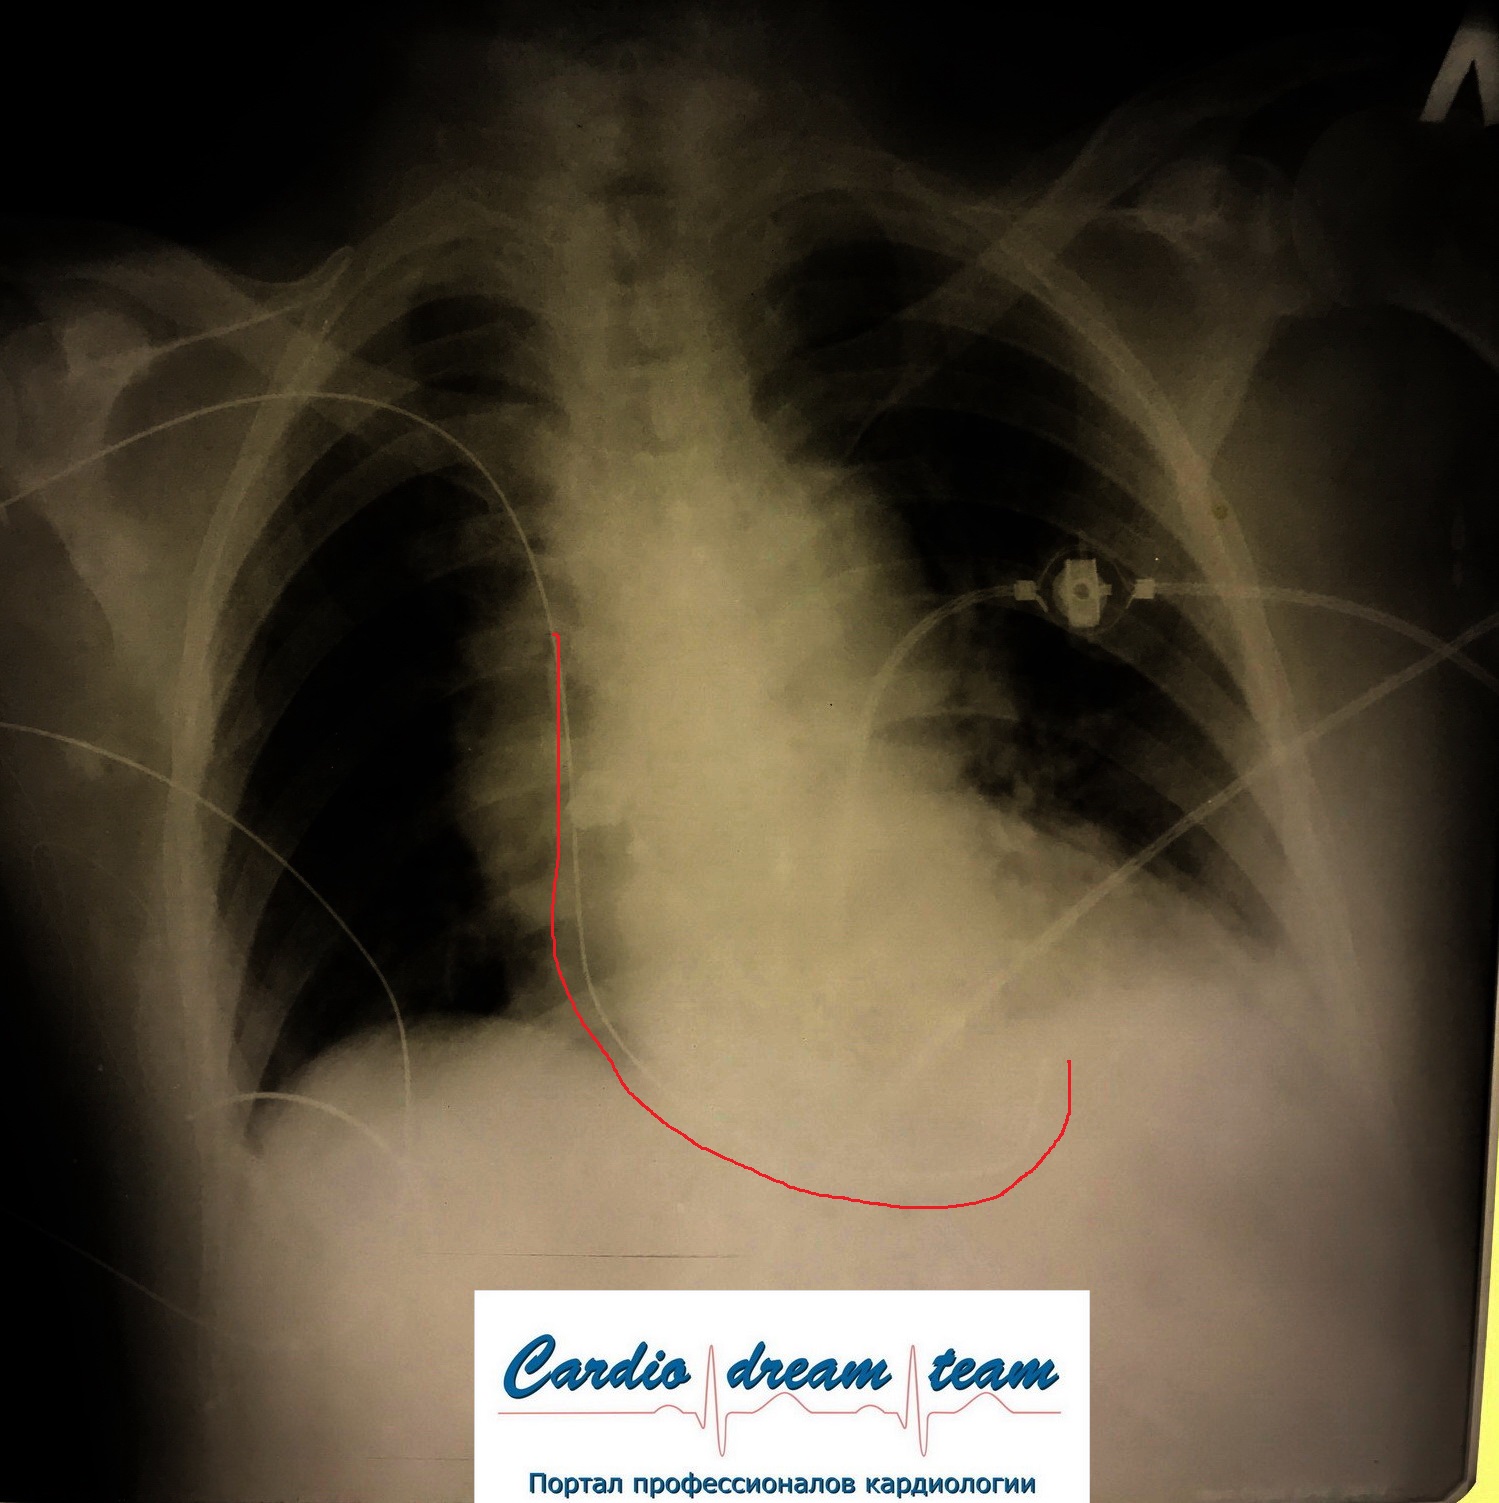

Гиповентиляция правого легкого потому, что интубационная трубка в правом легком. Конец трубки указан красным.

Не обсуждалось